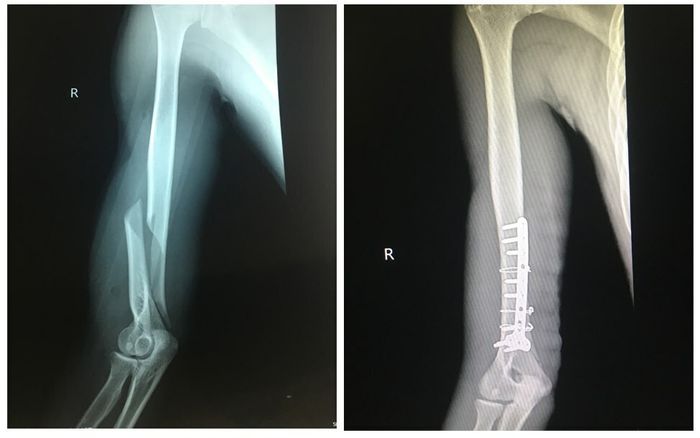

Gãy xương do chơi vật tay

Thanh niên 19 tuổi bị gãy xương cánh tay khi chơi trò vật tay, có thể cần tới 6 tháng để hồi phục.